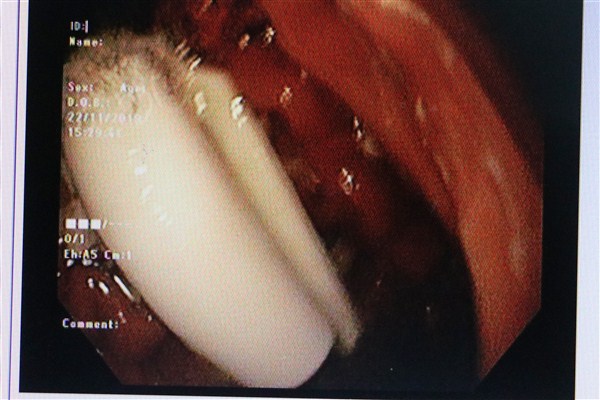

Nội soi thấy dị vật nằm ở bờ cong lớn dạ dày của bệnh nhân

Sau khi được đưa vào bệnh viện, bệnh nhân đã được tiến hành nội soi thực quản - dạ dày - tá tràng. Khi tiến hành nội soi, các bác sĩ phát hiện dị vật nằm ở bờ cong lớn dạ dày của bệnh nhân, kíp nội soi đã tiến hành gắp dị vật là một nắp bút mực có kích thước 3,5x1cm. Sau soi gắp, bệnh nhân M.. đã ổn định và có thể ra viện ngay trong ngày.